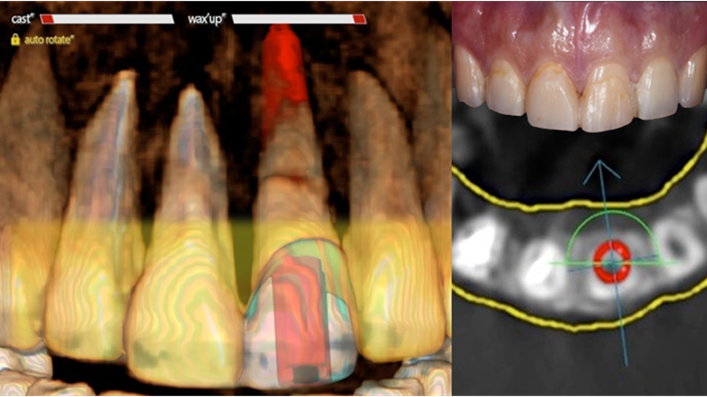

Clinical case: Extraction, immediate placement & loading using

R2GATE solution in aesthetic zone

- Courtesy of Dr. Jong-Cheol Kim, Korea-

Dr. Jong Cheol Kim, immediate loading, digital guided surgery, Digital ONE-DAY Implant, maxillary anterior, #21, guided surgery, immediate loading, AnyRidge, R2GATE, Mega ISQ, MEG Torq, R2GATE Full Surgical Kit